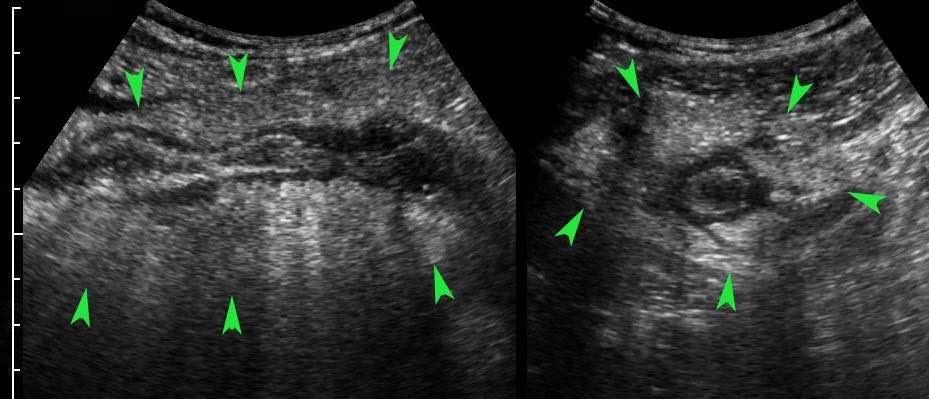

Bờ giảm âm không đều, bất đối xứng và mất cấu trúc phân lớp thành ruột thừa là dấu hiệu gợi ý thủng hoặc thủng sắp xảy ra.

Ở giai đoạn này luôn có mô mỡ viêm phong phú (đầu mũi tên).

Cấu trúc phân lớp thành ruột thừa càng bị tổn thương nhiều, khả năng thủng càng cao.

Dấu hiệu đầu tiên là những thay đổi giảm âm trong lớp dưới niêm mạc tăng âm.